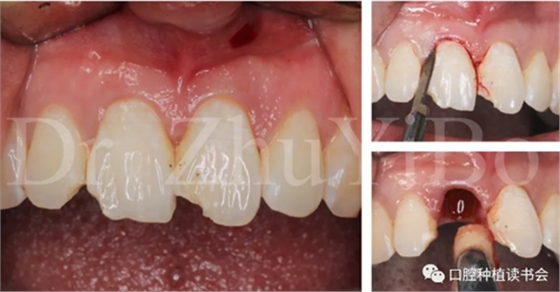

一位年輕女性患者,右上中切牙外傷冠根折2日。

臨床檢查發(fā)現(xiàn):右上中切牙冠根折,斷面位于齦緣下4到5個(gè)毫米。左上中切牙及右上側(cè)切牙,切角缺損,牙髓活力正常(圖7)。

圖7 外傷導(dǎo)致11冠根折

4.2.1微創(chuàng)拔出牙齒,挺出根尖(圖9)

圖9 斷裂牙根需用微創(chuàng)器械拔除

4.2.2 拔牙窩沖洗,定點(diǎn),備洞(圖10)。

圖10 種植窩洞相對(duì)于天然牙長(zhǎng)軸偏向腭側(cè)